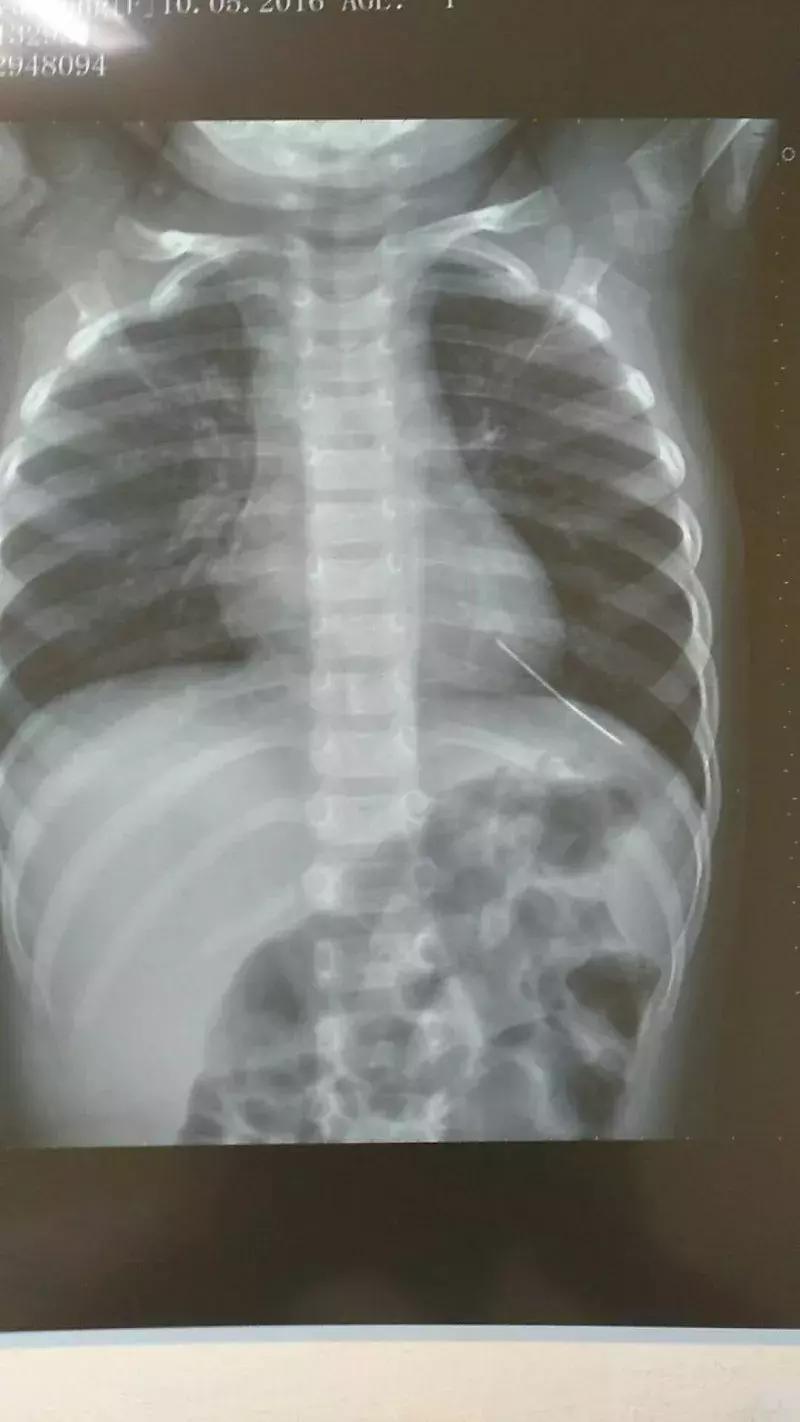

接诊的是心内科的王医师,因为家长说孩子夜里咳嗽剧烈,做了初步检查后,为了谨慎起见,他建议拍X光片查看肺部感染情况。

胸腔有异物!

谢先生带着辰辰拍完片后,一家人正准备离开,不料被放射科医生拦住了,询问他辰辰衣服上有没有金属,他和妻子觉得很意外,仔细检查一番发现没有。之后,医生要求他们把辰辰的衣服全部脱掉,并请来另一位经验丰富的医生,又给孩子拍了一次。

谢先生和妻子忐忑不安照做后,拍片的医生告诉谢先生:“我们确定孩子胸腔内应该是有异物。”“是什么东西?”谢先生和妻子吓了一跳。“看上去是一个高密度的金属物质,外形细长。”

夫妻俩赶紧拿着片子找王医师复诊。王医师看到片子后也是一惊,立即联系武汉儿童医院心胸外科的皮主任,将辰辰的片子发给了对方。“立即收进来,很可能要做急诊手术!”皮主任当即回复。

医院为辰辰开启绿色通道,以最快速度完善心电图、CT、心脏彩超等检查,初步圈定异物所在位置,在辰辰心脏的左室心尖部,约2毫米粗,外形像一根长针,需尽快取出。如果异物继续移动,可能会刺破心脏导致破裂出血,也可能随血液流动刺破血管,后果不堪设想。